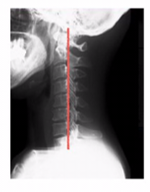

本来の頸椎は軽度前弯です。

ストレートネックから軽度前弯に変えていく必要があります。

ストレートネックだけの関節の動きだけでなく、この首からの脊柱のうごきを作る必要があります。

頸椎から背中の胸椎、腰椎と脊柱全体の連動したしなやかな脊柱が必要になります。